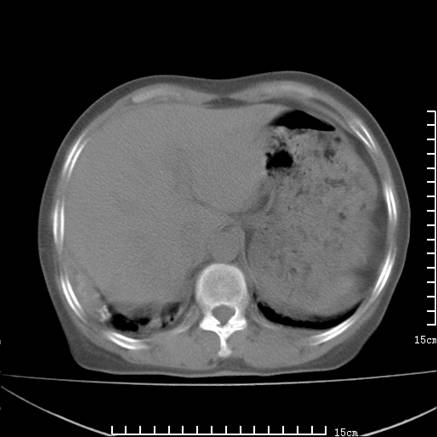

女,王某,58岁,咳嗽三个月余,基层医院二个月前诊为肺结核,用抗结核药二个月无明显疗效。

心包积液致肺瘀血.右侧周围型肺癌伴肺内转移,中间裂积液,叶间胸膜肥厚.右上肺大泡,右侧胸膜肥厚.

双肺继发型tb,心功能不全并肺淤血、心包、双侧叶间裂积液,肺大泡,右下胸膜肥厚钙化。

支持  双肺继发型tb,心功能不全并肺淤血、心包、双侧叶间裂积液,肺大泡,右下胸膜肥厚钙化。